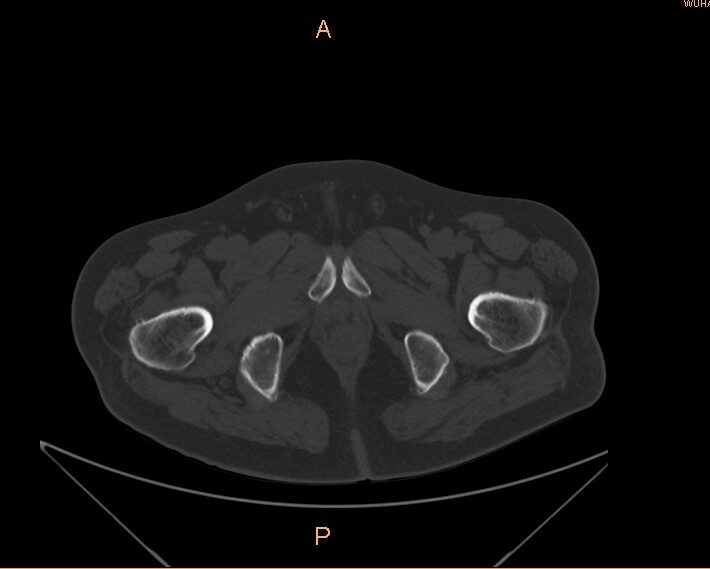

标题: CT29088:左股骨颈 [打印本页]

标题: CT29088:左股骨颈

左侧股骨颈疼痛。

左股骨颈软骨瘤可能,建议增强或mri

内生软骨瘤。

不排除骨样骨瘤

不排除左侧股骨颈内生软骨瘤可能。

内生软骨瘤年龄较小,分叶状,局部皮质有改变,钙化为环形半环形,没有这么粗大。

左股骨颈软骨瘤可能,建议增强或mri  。